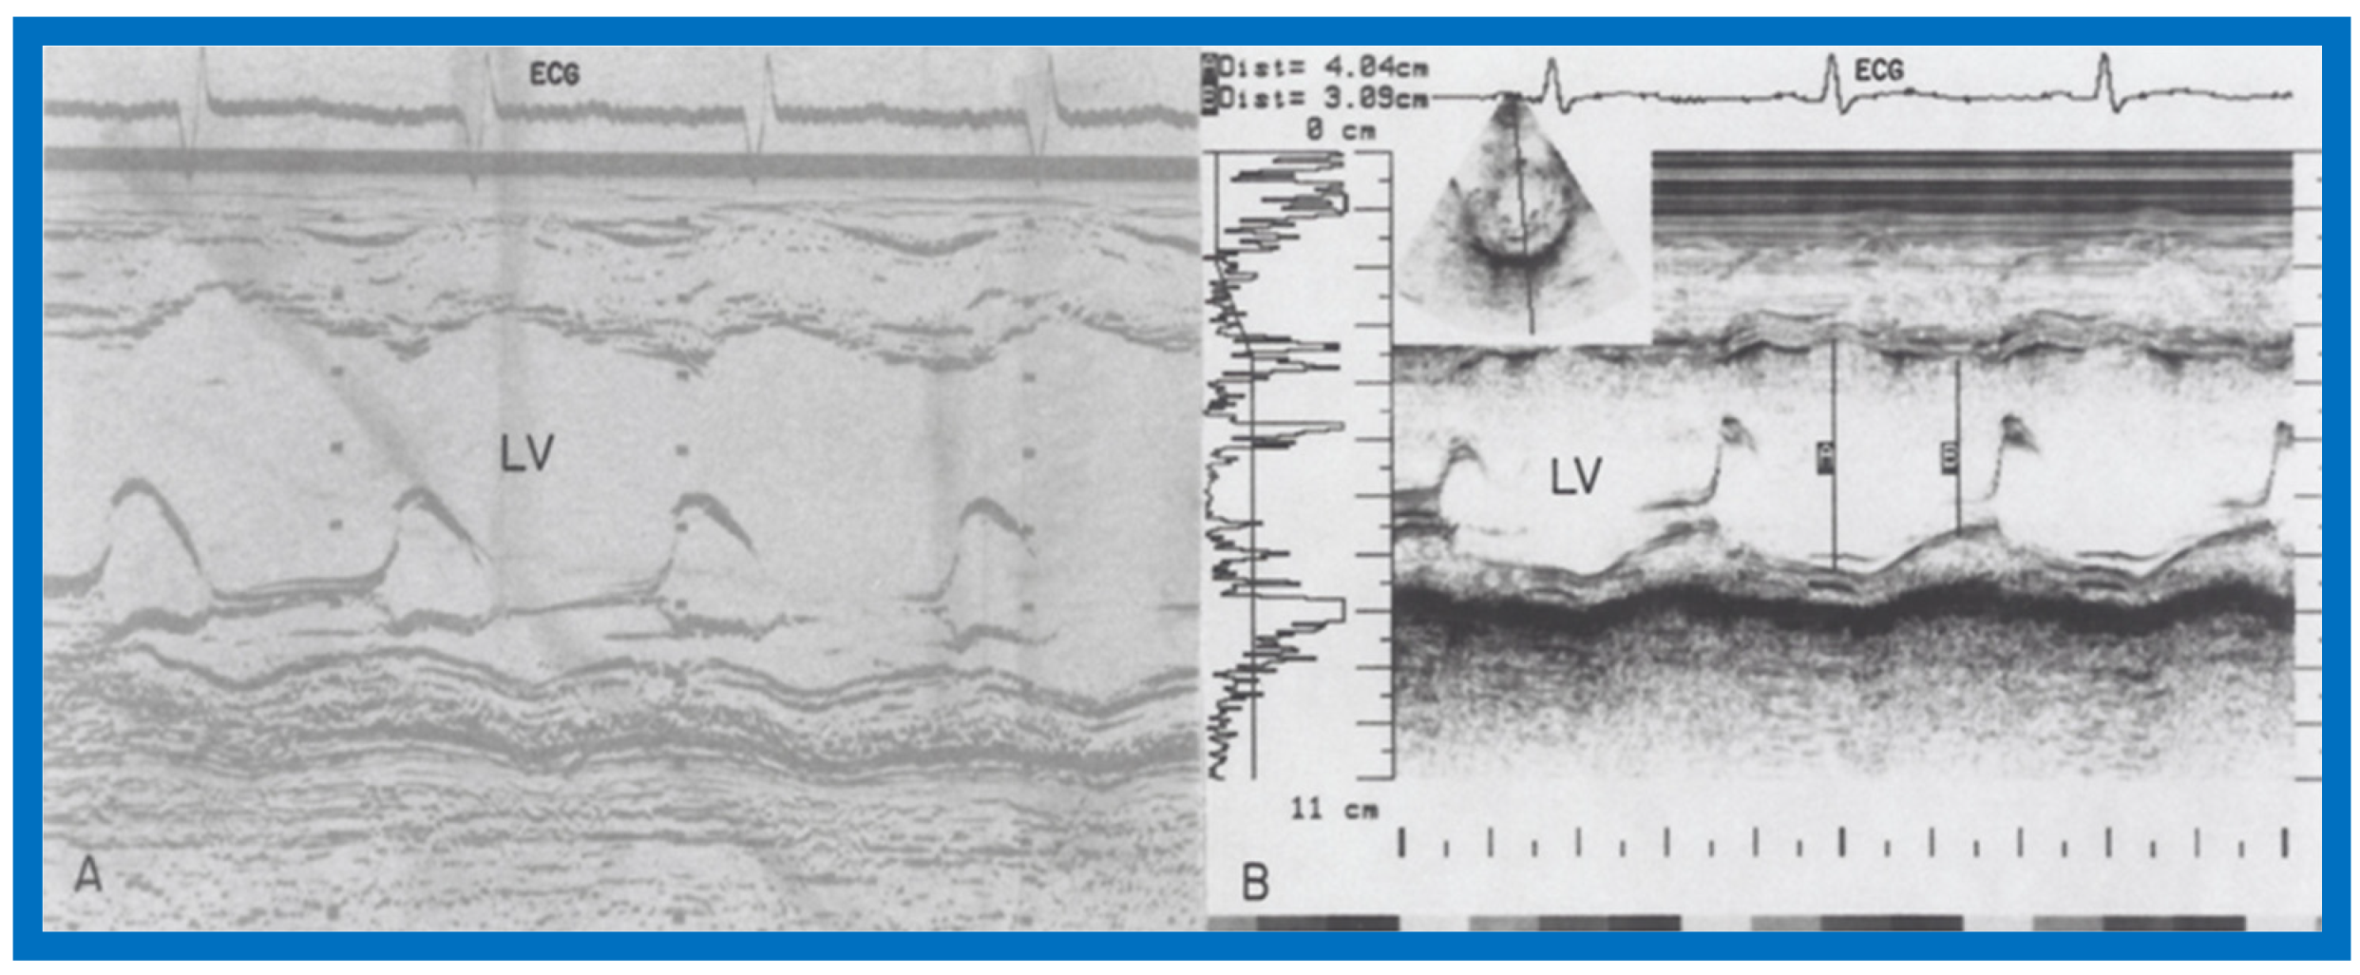

Figure 40.

Selected M-mode recording from the parasternal short axis view of the left ventricle (LV) prior to (A) and following (B) hydrazine therapy. Note the significant improvement in the LV size and function.

Figure 41.

Selected M-mode recording from the parasternal short axis view of the left ventricle (LV) prior to (A) and following (B) hydrazine therapy from a different infant. Also, note the significant improvement in the LV size and function.